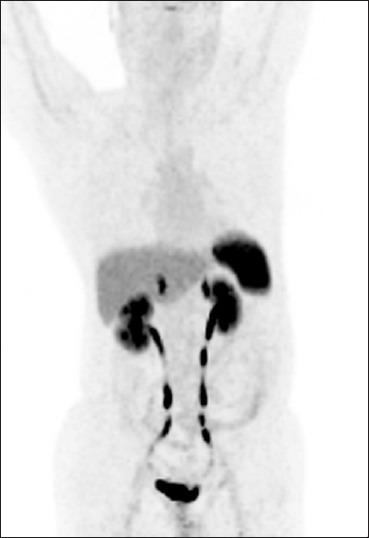

Neuroendocrine tumors (NETs) are rare neoplasms characterized by overexpression of somatostatin receptors (SSTRs). Functional imaging plays a crucial role in management of NETs. Recently, positron emission tomography/computed tomography (PET/CT) with (68)Gallium ((68)Ga)-labeled somatostatin analogues has shown excellent results for imaging of NETs and better results than conventional SSTR scintigraphy. In this review we have discussed the utility of (68)Ga-labeled somatostatin analogue PET/CT in NETs for various established and potential indications. In addition we have also shared our own experience from a tertiary care center in India.

神经内分泌肿瘤(NETs)是一种罕见的肿瘤,其特征是生长抑素受体(SSTRs)过度表达。功能成像在NETs的管理中起着至关重要的作用。最近,使用(68)镓((68)Ga)标记的生长抑素类似物的正电子发射断层扫描/计算机断层扫描(PET/CT)在NETs成像中显示出优异的结果,并且比传统的SSTR闪烁扫描结果更好。在这篇综述中,我们讨论了(68)Ga标记的生长抑素类似物PET/CT在NETs中用于各种既定和潜在适应症的效用。此外,我们还分享了我们在印度一家三级医疗中心的经验。